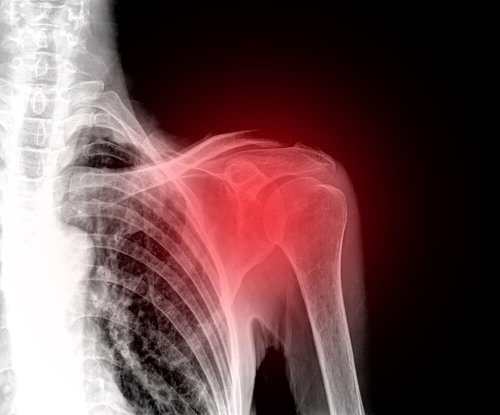

La spalla congelata è una condizione patologica e traumatologica che interessa l’articolazione della spalla. È anche conosciuta con il nome di capsulite adesiva, in quanto la manifestazione ultima dei sintomi è l’infiammazione della capsula della spalla.

Per capire questo meccanismo, dovremmo ripassare questa struttura scheletrica. Si tratta di un’articolazione che funge da punto di unione di tre importanti ossa: l’omero, la clavicola e la scapola, circondati da un tessuto molle che crea una capsula e che le avvolge. Questa capsula è la parte che si infiamma nel caso della spalla congelata.